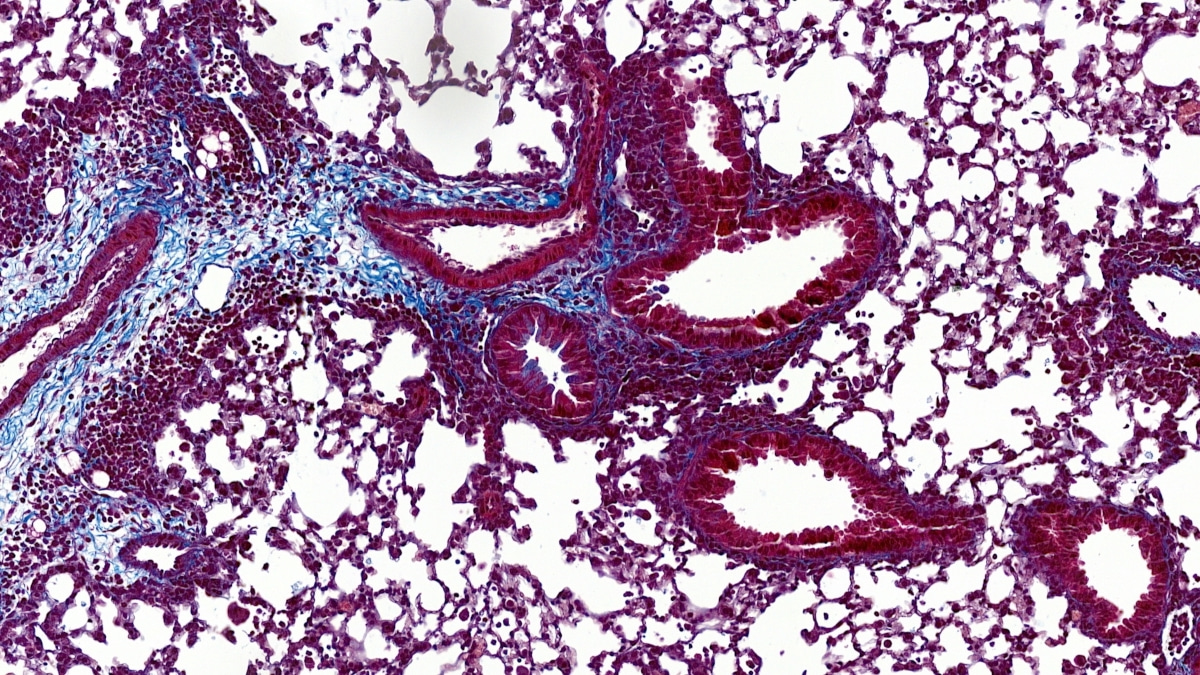

Deletion of ASB2 attenuates airway inflammation in mice. Control and ASB2 knockout mice were submitted to airway inflammation or treated with PBS (-). Compared to control mice, induction of airway inflammation in ASB2 knockout mice resulted in decreased immune cell infiltration determined by hematoxylin-eosin staining of lung sections, decreased remodeling of the airways evaluated by collagen deposits after Masson’s trichrome (MT) staining of lung sections, and decreased mucus secretion assessed after Periodic Acid Schiff’s staining of lung sections.